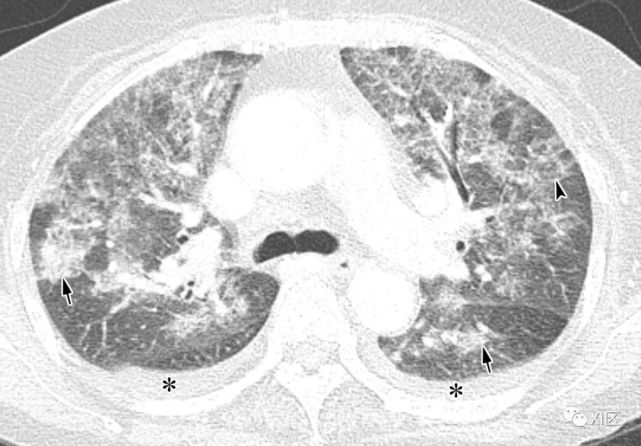

图13 63岁的男子,原发性中枢神经系统淋巴瘤化疗后合并发热,诊断为人博卡病毒肺炎

(上)胸部X线片显示两肺均弥漫性不规则斑块状实变(箭)和GGO。在同一天获得的轴位薄层(1mm)胸部CT图像显示,沿着支气管血管束和肺部周边区域出现不规则的斑块状实变(箭),支气管壁增厚,小叶间隔增厚 (箭头),伴有少量双侧胸腔积液(*)。

Koo H J , Lim S , Choe J , et al. Radiographic and CT Features of Viral Pneumonia[J]. Radiographics, 2018, 38(3):719-739.